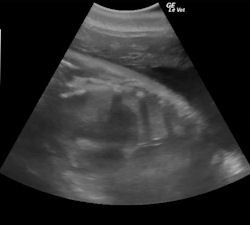

The oceanarium's staff studies the creatures' behavior and provides them with medical assistance by taking into account their clinical history and running cytology and blood tests. Imaging is useful to diagnose and treat the patients as soon as possible, and usually the first-choice modality is ultrasound.

"Ultrasound is versatile, easy to move and transport, noninvasive, and ideal to image soft tissues," said Crespo, an associate professor in the department of animal surgery and medicine at Cardenal Herrera University in Valencia. "Ultrasound equipment is designed to work with humans and pets. We have to use many probes and tricks to obtain sufficient image quality."

However, aquatic species have unique physical features that may reduce the penetration of the waves. Dolphins are sensitive to ultrasound frequencies and either need to be desensitized by medical training or get used to techniques such as harmonics.

Sea turtles' shells also can obstruct the examination. The carapace and plastron are made up of about 60 bones and the outer layer of the shell is covered by horny scales that prevent evaluation. The inguinal fossa, axillar area, or cervical access are the only acoustic windows available for assessment of follicular development and buoyancy problems, as well as a coelomic examination, which is the main region of interest for an ultrasound scan.

Ultrasound can be used for daily routine checks of the abdomen, soft tissues, and respiratory apparatus. Vets especially look for the presence of renal calculus, gastritis, foreign objects, and pleurisy or pneumonia, all of which are common scenarios in animals in captivity. Also, preventive medicine is a key aspect in conserving aquatic species, since these patients do not tend to complain.

A special interest of zoologists and marine biologists in the captivity setting is to monitor reproduction by evaluating the animals' reproductive tract. Imaging can be useful to know how well a pregnancy is going, when the baby is due, and if medical help is needed.

For instance, Crespo's team was able to save a baby dolphin during a complicated birth, thanks to the cord measurements taken on ultrasound. "The cord could have strangled the baby, but we knew the size and managed to deliver him safely. Further births were also successful using the information provided by ultrasound," he said.